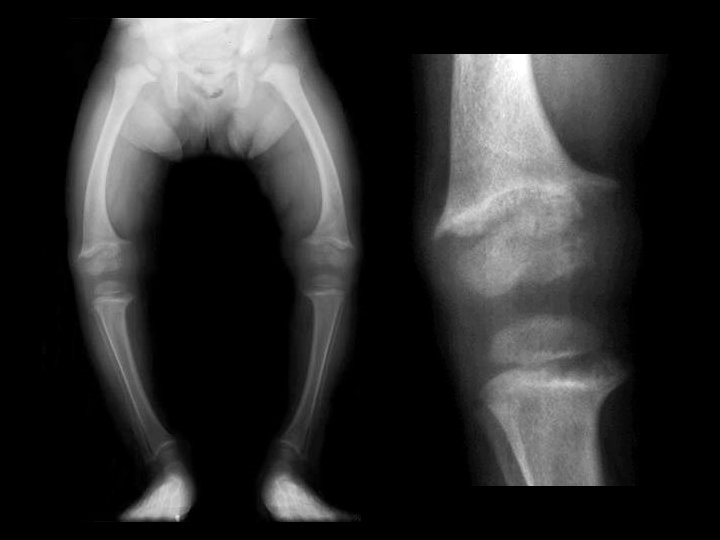

Renal osteodystrophy • Findings: – Osteopenia – Prominent trabecular pattern – “rugger jersey” spine • ddx: – NONE! – This is an Aunt Minnie!